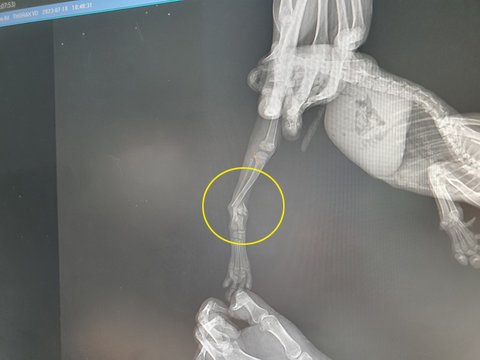

한참 기다리다 사진을 찍어보니 사람으로 치면 발목부분이 완전히 부러졌다고 한다.

거기다 너무 어려서.. 수술부위도 힘든 부위라 외과전문병원을 추천해주셨다. (동물병원도 외과전문병원이 있는지 이번에 처음알았음!)

수술하기 힘든 부위지만 어리다고 수술을 안하면 살짝 붙은 자리가 손가락만 튕겨도 계속 부러질거라고..